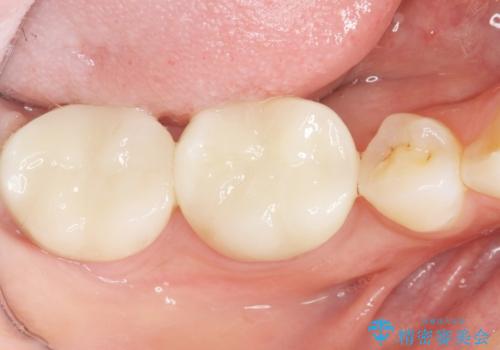

矯正せずに隙間を閉じることができ、ご満足頂けました。

セラミッククラウンの審美的な仕上がりと咬み心地に喜んで下さいました。

クラウンの種類:オールセラミッククラウン スタンダード